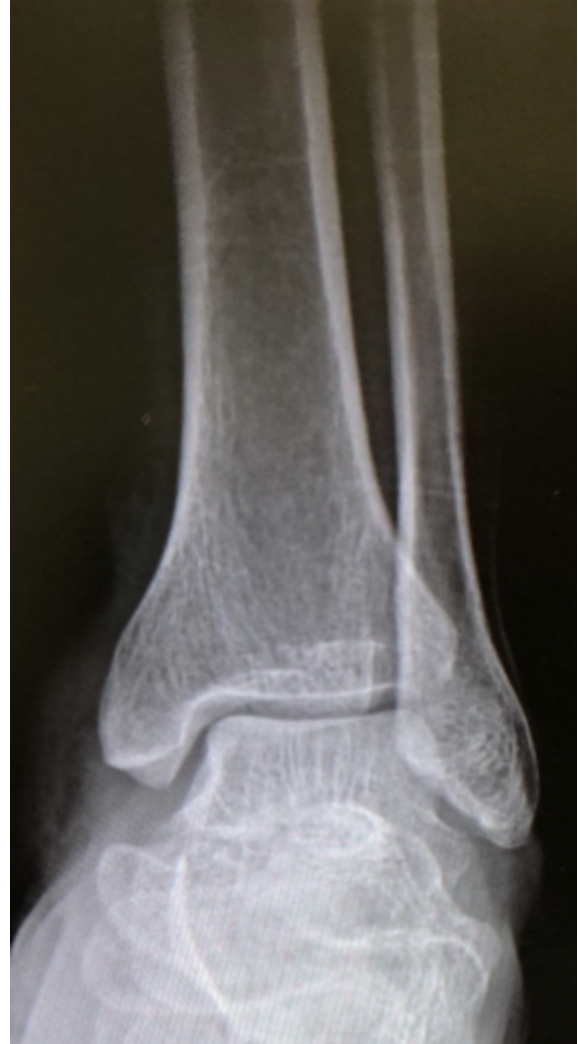

Q

What view is this?

A

Ankle AP